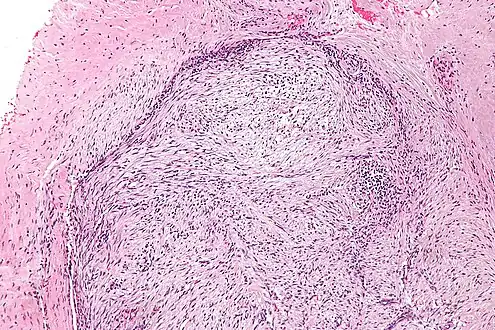

The microscopic histopathology of hematoxylin and eosin stained nodular fasciitis tumors (see above and three below figures) consists of spindle-shaped myofibroblastic cells (i.e. cells with features of smooth muscle cells and fibroblasts.).[9] These cells are in a myxoid (i.e. more blue or purple compared to normal connective tissue because of excessive uptake of the hematoxylin stain) or a collagenous (high content of collagen fibers) tissue background. The neoplastic myofibroblasts are arranged in whorls and/or short bundles. These cells may show high rates of replicating as judged by their mitotic index but these mitoses are normal in appearance. The tumor tissues often contain red blood cells, lymphocytes and giant osteoclast-like giant cells and may contain sites of bone-like tissue.[11] NF is sometimes classified into three subtypes based on its predominant histopathological pattern: myxoid or reactive (type I), cellular (type II), and fibrous (type III).[5] These patterns appear related to the duration of the lesion with the myxoid variant tending to have the shortest duration and the cellular and fibrous variants tending to have progressively longer durations.[15]Immunohistochemical analyses indicate that the cells in NF usually express smooth muscle actin, muscle specific actin, and vimentin proteins but generally do not express CD34, S-100 protein, desmin, trypsin, factor VIII, F4/80 (also termed macrophage-specific antigen), or HLA-DR1 proteins.[11] Uncommonly, the cells in NF tumors also express the CD68 (a histiocyte-specific marker) protein.[5]

Low magnification -